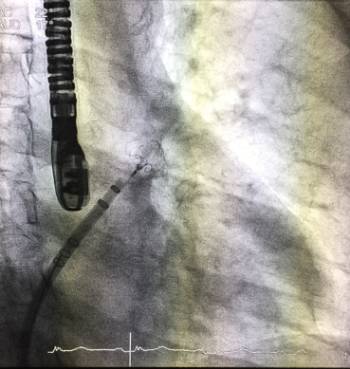

Actualmente el cierre percutáneo de la orejuela izquierda (OI) es una técnica reciente y alternativa segura y eficaz para la prevención de ictus en pacientes que presentan contraindicaciones para anticoagulación con inhibidores de la vitamina K o nuevos anticoagulantes orales (NACOS).

La idea en la que se basa esta técnica es la de excluir de la circulación dicha estructura, evitando así que sea fuente de trombos en estos pacientes. En el ensayo PROTECT-AF, publicado en Lancet en el año 2009, la oclusión percutánea de la orejuela auricular izquierda mediante el dispositivo Watchman (Boston Scientific) demostró ser no-inferior a la anticoagulación oral (1,4% ictus/año Vs 1,1%, es el riesgo de ictus anual). Estudios y registros posteriores han confirmado su utilidad.

El procedimiento realizado por vía percutánea femoral, se llevó a cabo con éxito recientemente por parte de los doctores Jorge Palazuelos Molinero, responsable de la Unidad de Hemodinámica del Hospital La Luz, José Antonio Fernández Díaz e Ignacio Cruz González, miembros del Equipo de Cardiología Clínica e Intervencionista del Dr. Roberto Martín Reyes, del centro sanitario.